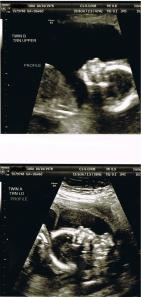

But anyway! One of each!! It is so exciting! Boy Baby is a little bit bigger than his sister already. They are kind of lying perpendicular to each other. It is sort of odd. We go back for another growth scan in 5 weeks.

I really enjoyed seeing shots of their profiles. Maybe all babies look the same in utero, I don’t know. All of my babies distinctly show Ed’s lips and my nose though. Baby B, the boy baby on the top…already looks just like Eddie in there. It’s uncanny. We didn’t get a great shot of Baby A, because she NEVER stops moving. I can see it though.